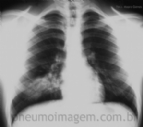

DESTAQUES DO CHEST 2015: COLONIZAÇÃO, ANTIBIÓTICO INALATÓRIO E MACROLÍDEOS EM BRONQUIECTASIAS